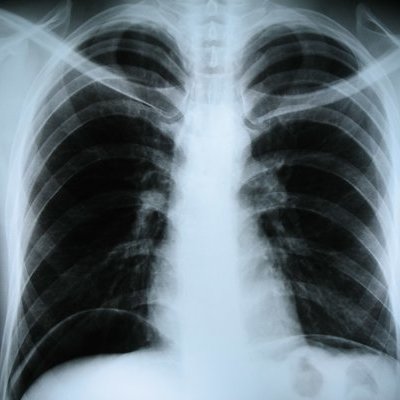

Нидерландские исследователи из Университета Гронингена обнаружили, что значительная часть некурящих пациентов имеет твердые легочные узелки, которые могут быть ранним признаком рака легких.

Результаты исследования, опубликованные в журнале Radiology, показывают, что среди более чем 10 тысяч обследованных участников, 46,1% никогда не курили, а 53,9% бросили курить к моменту проведения скрининга.

Компьютерная томография выявила хотя бы один узел в легких у 42% участников, при этом у 11,1% из них узелки достигали клинически значимого размера в 6-8 миллиметров. Ученые подчеркнули, что наличие таких узелков у некурящих, которые обычно считаются группой низкого риска, оказалось выше ожидаемого и сравнимо с данными для курильщиков.

Однако, несмотря на это, заболеваемость раком легких среди некурящих остается низкой — всего 0,3%, и большинство выявленных узелков оказываются доброкачественными.